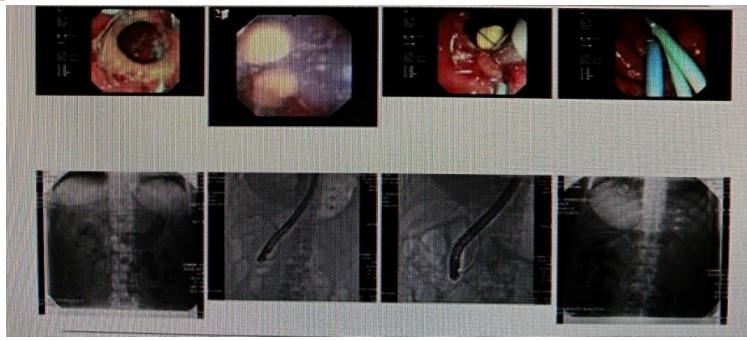

消化內(nèi)科肝病亞??茍F(tuán)隊(duì)詳細(xì)討論,分析患者情況后,取消了周女士的肝穿刺活檢檢查,建議患者先行超聲胃鏡下膽胰掃查。在內(nèi)鏡醫(yī)師第三只眼——超聲胃鏡的掃查下,發(fā)現(xiàn)引起周女士肝功能受損的罪魁禍?zhǔn)?/span>原來是膽總管末端結(jié)石!伍友興主任醫(yī)師帶領(lǐng)團(tuán)隊(duì)給予患者行ERCP下取石后,周女士未再出現(xiàn)腹痛,肝功能恢復(fù)正常。

無獨(dú)有偶,劉先生也為反復(fù)出現(xiàn)肝功能受損到多家醫(yī)院就診檢查,未能找到原因,來到衡陽(yáng)市中心醫(yī)院消化內(nèi)科就診,希望能在肝穿刺活檢下得出病因。在行肝穿刺活檢之前,醫(yī)生建議劉先生行超聲胃鏡膽胰掃查,發(fā)現(xiàn)引起劉先生反復(fù)肝功能受損原因,亦是膽總管結(jié)石引起,在ERCP術(shù)取石術(shù)后,患者肝功能恢復(fù)正常,未再出現(xiàn)異常情況。